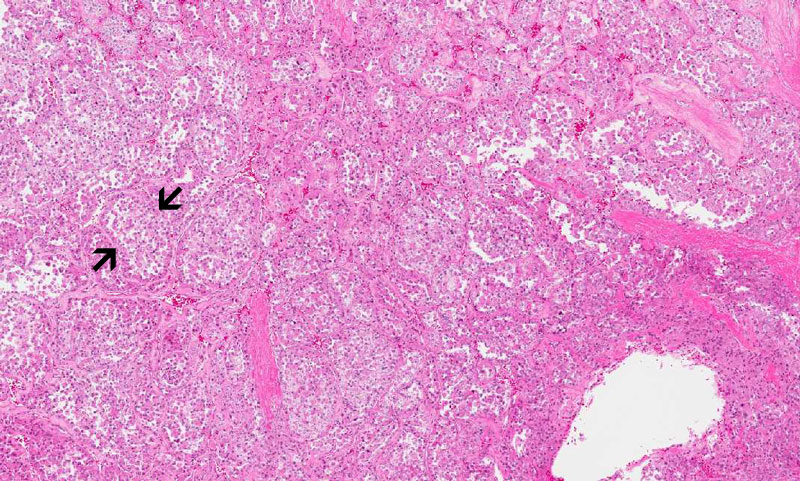

Hematoxylin & eosin

High magnification: The pleomorphic nuclei can be well appreciated. The tumor is present in a location just under the endothelial cells. Note the lumen of the vessel (V)